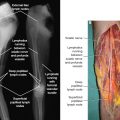

Compared with a passive component, the essential characteristic of an active component of the immune response is the ability to respond to diverse stimuli and change effector function in response to these diverse stimuli. For example, different activation signals induce different activation programs in macrophages and T cells, such as the classic M1/M2 macrophage responses or Th1/Th2 T-cell responses. This differential integration of signals allows functional specialization and active immune regulation. In contrast to their perceived role as a passive conduit for immune cells, the lymphatics can respond to a wide range of pathogenic stimuli (the socalled primary activation signals) and immune molecules (the socalled secondary activation signals), all of which induce different functional outcomes in immune cell activation/migration and lymphangiogenesis (Fig. 11-1).